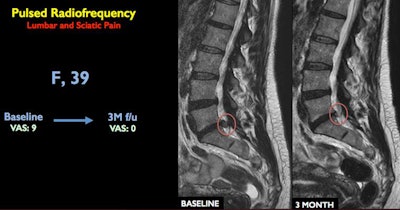

Lumbar spine MRI scan shows vertebra at baseline and three months after treatment. Image courtesy of RSNA.Lumbar spine MRI scan shows vertebra at baseline and three months after treatment. Image courtesy of RSNA.

An image-guided interventional radiology (IR) treatment using pulsed radiofrequency was able to relieve pain symptoms in a majority of patients with low back pain and sciatica, according to a presentation by Italian researchers on November 29 at this week's RSNA 2017 meeting in Chicago.

Under CT guidance, interventional radiologists inserted a needle at the location of the bulging disk and nerve root. The clinicians then inserted a probe through the tip of the needle that delivered pulsed radiofrequency (RF) energy to the problem area over a 10-minute period. The RF energy resolves the herniation without touching the disk, Napoli reported.

Of the 80 patients who received a single 10-minute treatment, 81% reported they were pain-free after a year. Six patients needed a second pulsed RF session, and 90% of the patients were able to avoid open surgery.